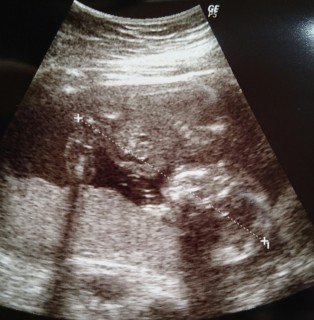

写真:18w0d:ぴーママさん:指しゃぶり

BPD(頭の幅) 45.3ミリ AC(腹部周囲長) 129.2ミリ FL(大腿骨長) 25.1ミリ 体重は225グラム、頭からお尻まで13センチで足を伸ばせば20センチ弱とのこと。 順調だそうです♪ 『ぜひとも性別をお願いします!』で、エコー開始数秒で写真の通り男の子と判明(笑)。 お母ちゃんの気持ちが伝わったかな? 地味に動いていてかわいかった~♪ 胎動はこれかな?というのはあるのですが、確信が持てず…。 先生は全然問題ないですよーとおっしゃっていました! 次回4週間後も楽しみです(^∀^)